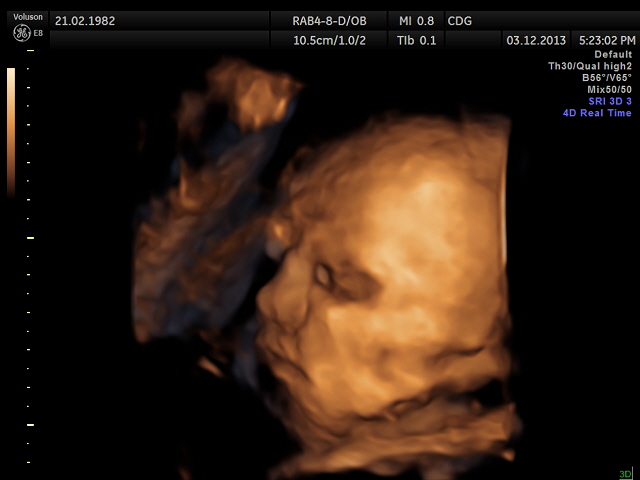

ВОт наша маленькая крошка-Катюшка!!!)))

Очень сложно было сделать фото, прикрывалась обеими ручками и пуповина перед лицом.

Потому качество не ахти!! Но мне все равно кажется, что красотка)))